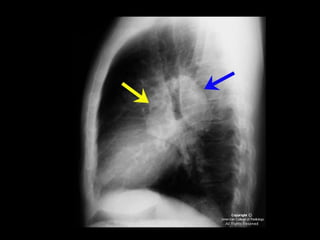

Exames de imagem: Rx Tórax

Primeiro passo na investigação radiológica da

suspeita de HAP;

Achados típicos: aumento do calibre das artérias

centrais, com rápido afilamento dos vasos à medida

que progridem para a periferia;

A área cardíaca pode estar aumentada ou normal;

Calcificação vascular: associado a alta RVP;

Sensibilidade baixa;

Útil para afastar ou sugerir causas de HAP;

Radiografia de tórax normal